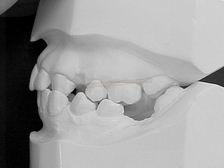

MODELOS DE ESTUDO EM GESSO (vista latera direita) |

MODELOS DE ESTUDO EM GESSO (vista latera esquerda) |

MODELOS DE ESTUDO EM GESSO (vista frontal) |